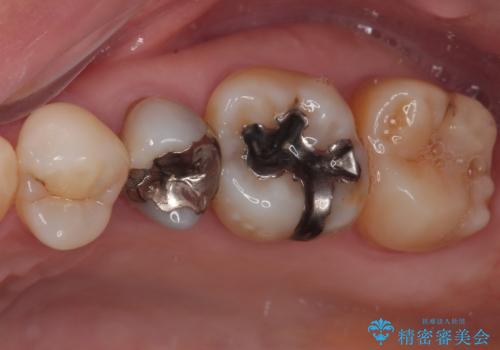

- むし歯と銀歯を気にして来院された患者様です。

銀歯の歯は既に根管治療がされており、根尖部に病変が認められないため、根管治療を行うことなくオールセラミッククラウンにて補綴治療を行うこととしました。

むし歯の症状のある歯は、ややしみることがある程度でしたが、レントゲン写真では非常にむし歯が大きく、神経組織に迫っている状態でした。

術前診査では神経を全て取る可能性は低いと予想されましたが、一部切除する可能性があることを伝えた上で治療を行うこととしました。